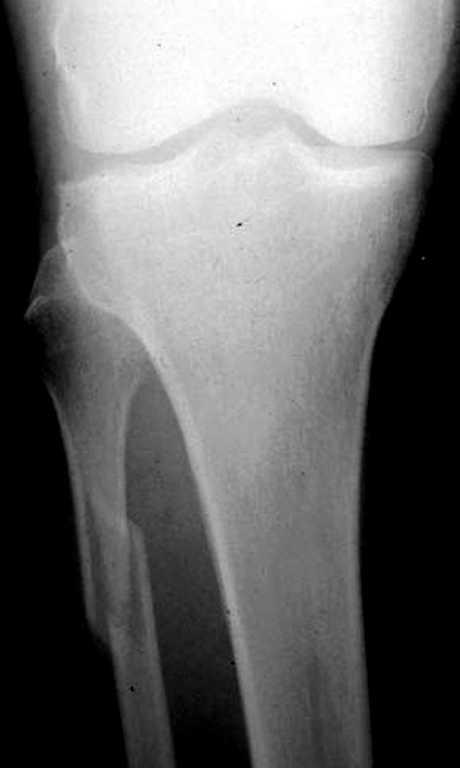

При проксимальных переломах малоберцовой автоматически необходимо подозревать повреждение синдесмоза - Maisonneuve Fracture.

"На западе", как правило, при переломах голеностопа требуются снимки проксимальной части голени.

Описанное в 1840 году Maisonneuve повреждение характеризуется тем, что при фиксированной наружной ротации стопы повреждается передняя фибуло-тибиальная связка, часть синдесмоза, с переломом медиальной лодыжки и без, дальше разрыв продолжается по межкостной мембране и спиральный или косой перелом малоберцовой происходит выше.